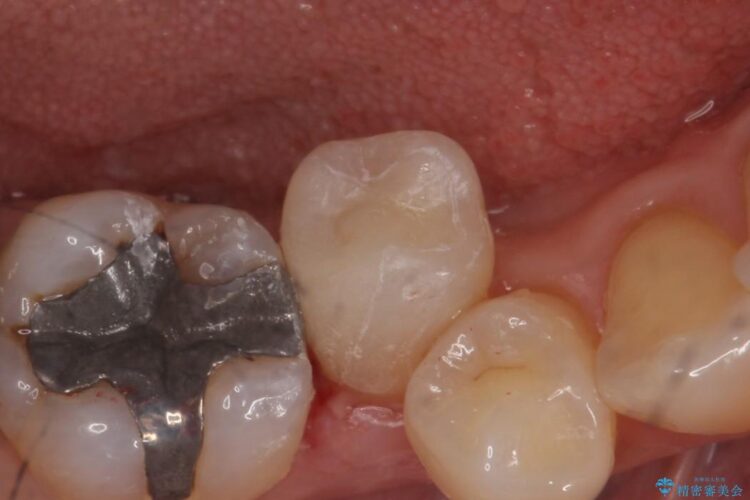

口腔内を調べたところ、右下5番の歯の詰めの下に虫歯を認めました。歯が舌側にズレていて歯磨きをしづらい位置なこともあり、虫歯が再発している状態でした。

虫歯部分を丁寧に取り除き、見た目の問題から患者様のご希望もあり、変性の少ないセラミックインレーを用いて機能と見た目の回復をする計画としました。